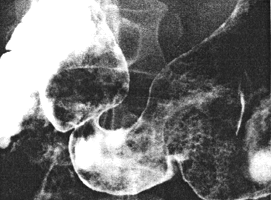

Case 35.2M.B., 59 year old female presented with dysphagia. Oesophagoscopy and biopsy revealed a poorly differentiated squamous cell carcinoma of the oesophagus at 26.0cm. Radiography confirmed the lesion, which appeared to extend to just above the cardia. There was constant contraction of the pyloric sphincteric cylinder, which appeared to be "fixed" midway between maximum contraction and relaxation, with absent cyclical activity; this caused the pyloric aperture to remain widely patent (Fig. 35.2). Laparotomy for staging the oesophageal carcinoma revealed metastatic lymphadenopathy at the coeliac axis; the stomach appeared normal, showing that the contraction of the sphincteric cylinder was of a functional nature.

| Fig. 35.2. Case M.B. Double contrast examination. Constant contraction of pyloric sphincteric cylinder with absent cyclical activity. Pyloric aperture patent. |